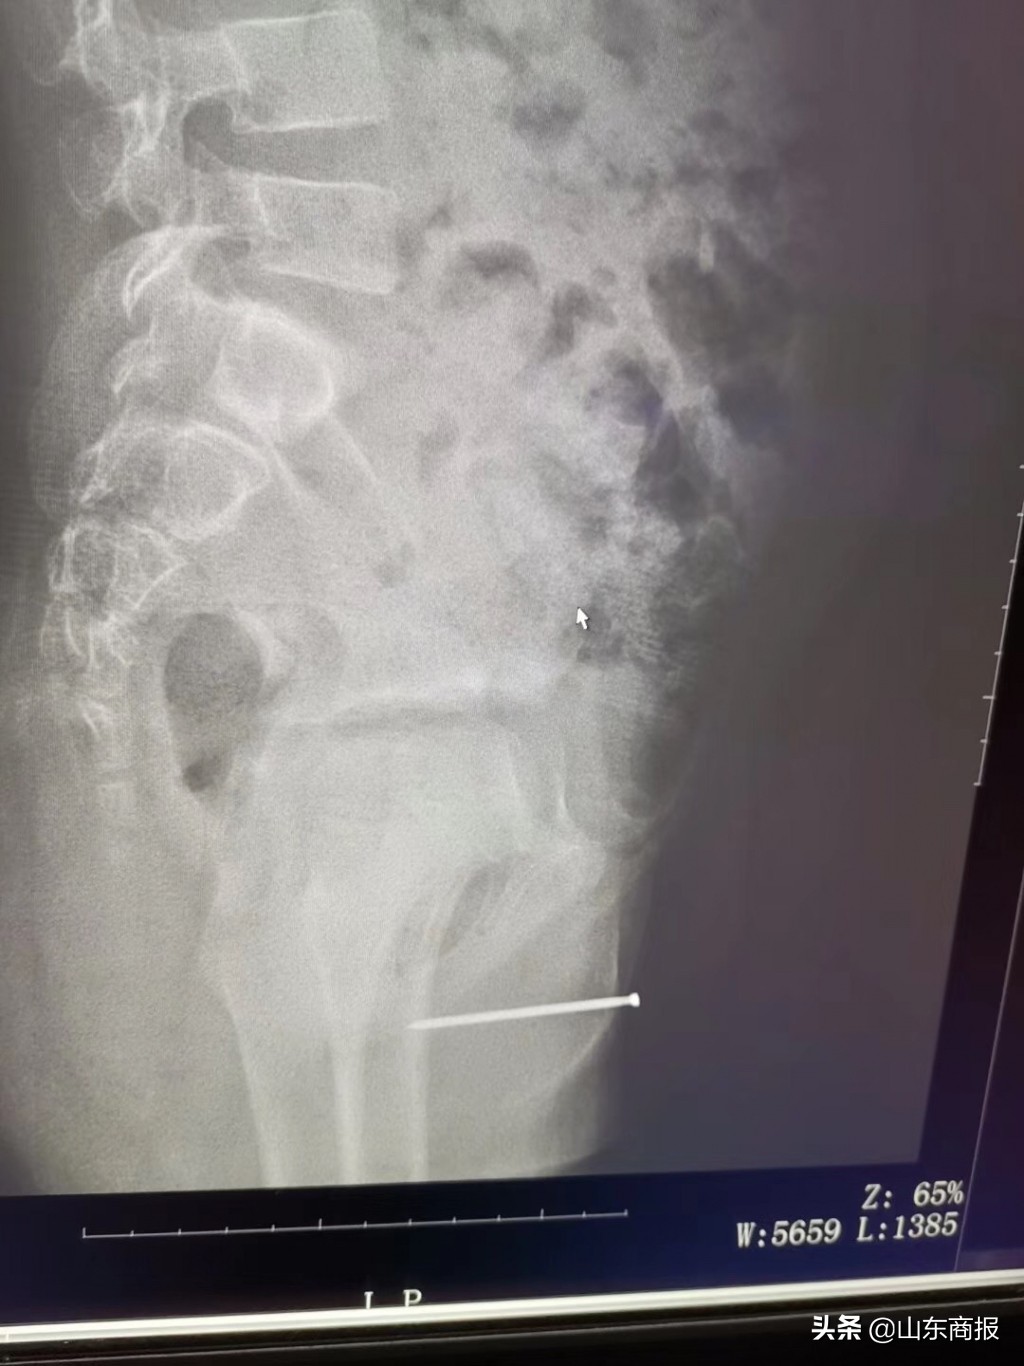

医生检查时,患儿尿道外口仍见少量脓性分泌物,尿道内可扪及明显异物。各项检查结果出来,也让异物慢慢显出原形,小明的尿道异物疑似铁钉。

2 月 13 日上午,医生通过输尿管镜尿道膀胱镜检手术成功将异物取出,在场的医护人员都大吃一惊,原来小明尿道内的真是一颗铁钉,长约 4.7cm,明显锈迹斑斑。